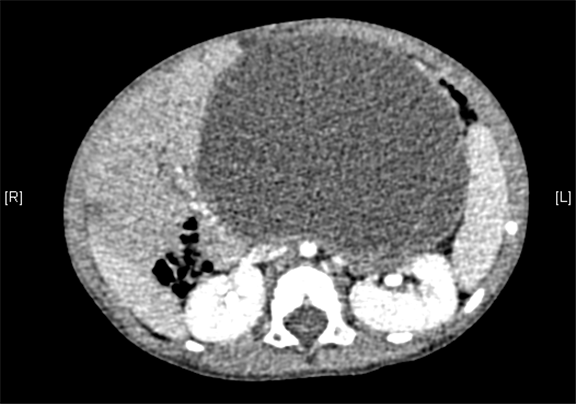

腹部三维动态CT:腹腔巨大囊性占位性病变,考虑肠系膜来源良性病变可能性大,腹腔肠系膜淋巴管瘤?

术前CT检查:

动脉期

静脉期

平衡期